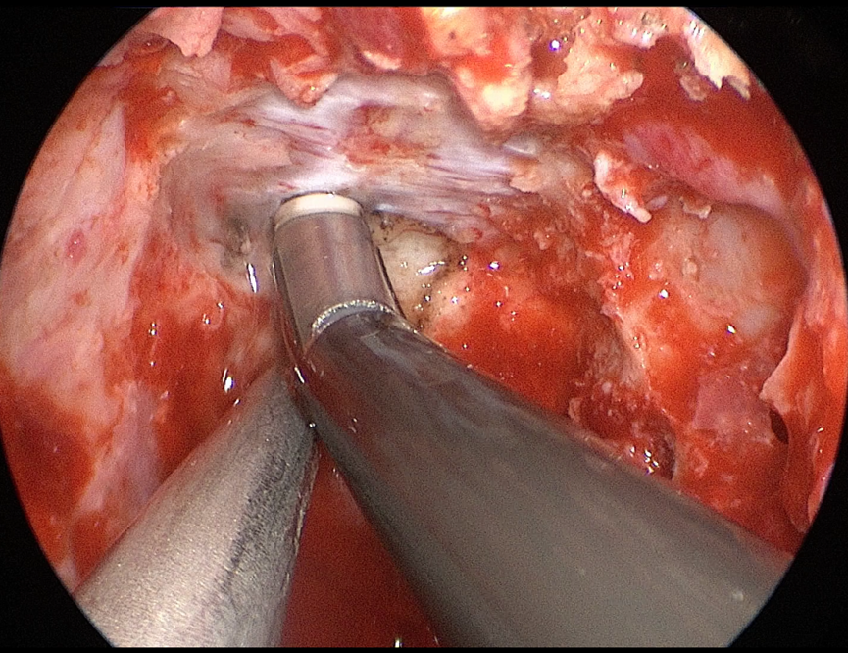

自近蝶窦前壁处向左侧推挤鼻中隔,离断筛骨垂直板,咬除部分近蝶窦处骨性鼻中隔,分离双侧鼻粘膜显露蝶窦前壁,自蝶窦开口上方做沿鼻中隔做粘膜瓣备用,末端到中鼻甲位置,将粘膜瓣压向下鼻道,高速磨钻磨除蝶窦下壁骨质,鞍结节骨质。术中视神经管清晰可见,给予保护,海绵间窦出血给予流体明胶+凝血酶止血;等离子刀一边止血一边切开硬脑膜见白色肿瘤质韧,边界清晰,大脑前动脉分支粘连于肿瘤表面,给予小心分离,以刮圈,咬切钳等小心清除肿瘤组织;内镜下将肿瘤完整切除;取右侧大腿皮下脂肪及阔筋膜备用,以人工硬膜修补和明胶海绵封闭鞍底硬膜,将脂肪放置于切口,并缝合于鞍底硬脑膜上固定铺平,阔筋膜覆盖于脂肪外边,蝶窦内充填明胶海绵止血,鼻粘膜瓣覆盖于蝶窦;碘仿纱条填塞鼻腔;护士清点棉条、器械、纱布无误,撤出鼻镜。